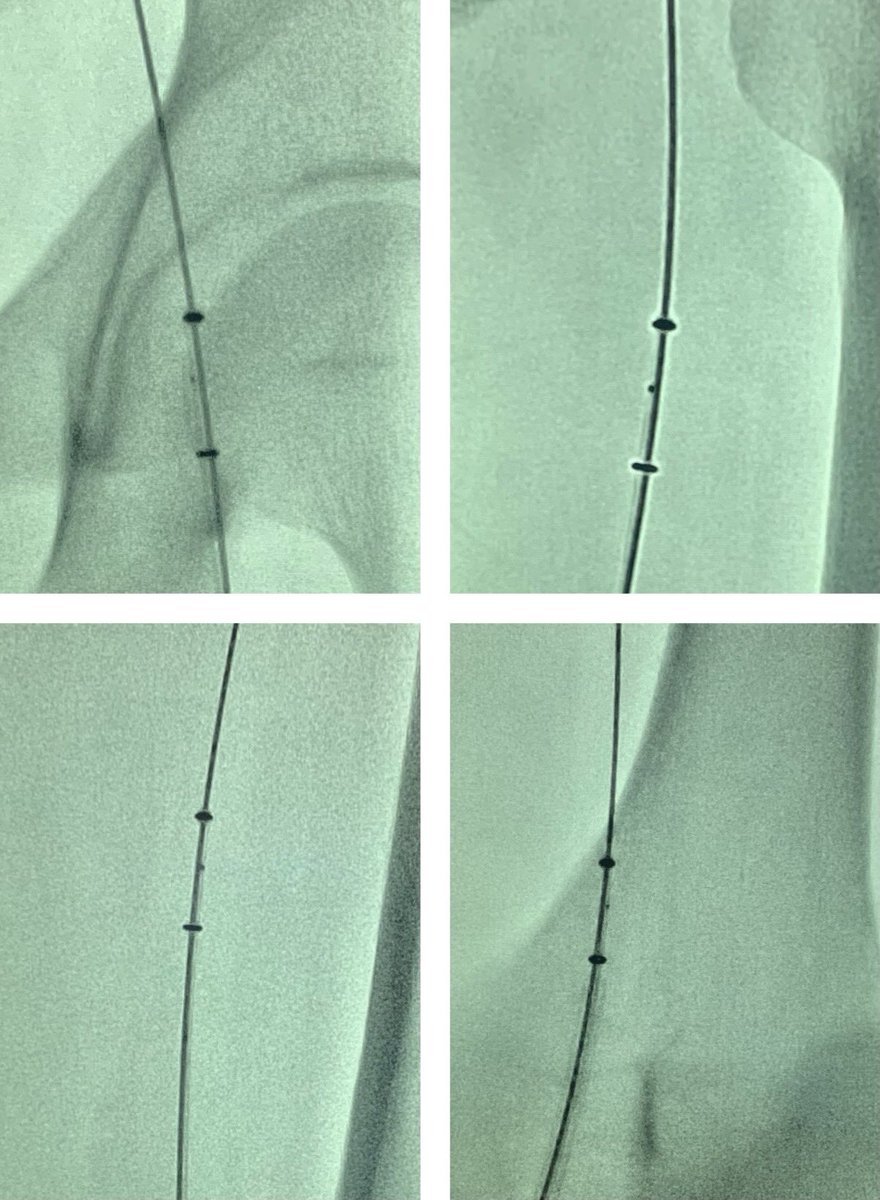

How distal can you track an AngioJet Dista device? @bostonsci @_backtable @Vascupedia_com @CLI_Global